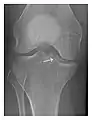

Triquetral fracture usually occurs on the dorsal aspect by impingement from the ulnar styloid or avulsion of strong ligamentous attachment. The dorsal avulsion fracture or "chip fracture" appears as a small bony fragment on the dorsal aspect of the triquetrum and is best detected on the lateral view(Figure 4). When radiography is negative in patients with high suspicion of a fracture, both MRI and MDCT will be of value. However, it has been shown that MRI is superior for detecting trabecular fractures in carpal bones.

Figure 4: Dorsal triquetral fracture of the left wrist in a 30-year-old man after a trauma. (a) Anteroposterior radiograph shows a normal appearance. (b) Lateral radiograph of the same wrist demonstrates a chip fracture off the dorsal aspect of the triquetrum (arrow).[1]